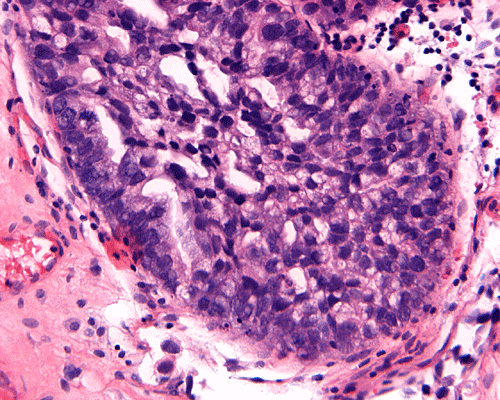

On scanning-magnification, the biopsy material consists of small nodules of stromal tissue with epithelium lined papillae (Panel A). On low-magnification (Panel B), both multilayered epithelium  and cribiform pattern (Panel C)are demonstrated. On high-magnification  (Panel D), the epithelial cells are hyperchromatic and pleomorphic. Intracytoplasmic mucin is well demonstrated by periodic acid-Schiff (PAS)- Alcian blue stain (Panel E) and mucicarmine stain (Panel F). No invasion is demontsrated.

Histologically, in situ adenocarcinoma is defined as a noninvasive glandular lesion, where the mucosa of the urinary bladder is replaced by an atypical, often pseudostratified columnar epithelium, featuring atypical cytoplasm and definitive cytologic atypia with nuclear hyperchromasia, moderate to severe nuclear pleomorphism, frequent mitosis and apoptosis 4. Necrosis is infrequently seen.

Three distinct architectural patterns have been described: papillary, cribriform and flat 2, 3, 4. Papillary architecture is the one most commonly seen, followed by cribriform pattern. Individual cases rarely show a pure pattern; rather, various combinations of the three patterns are more often seen.